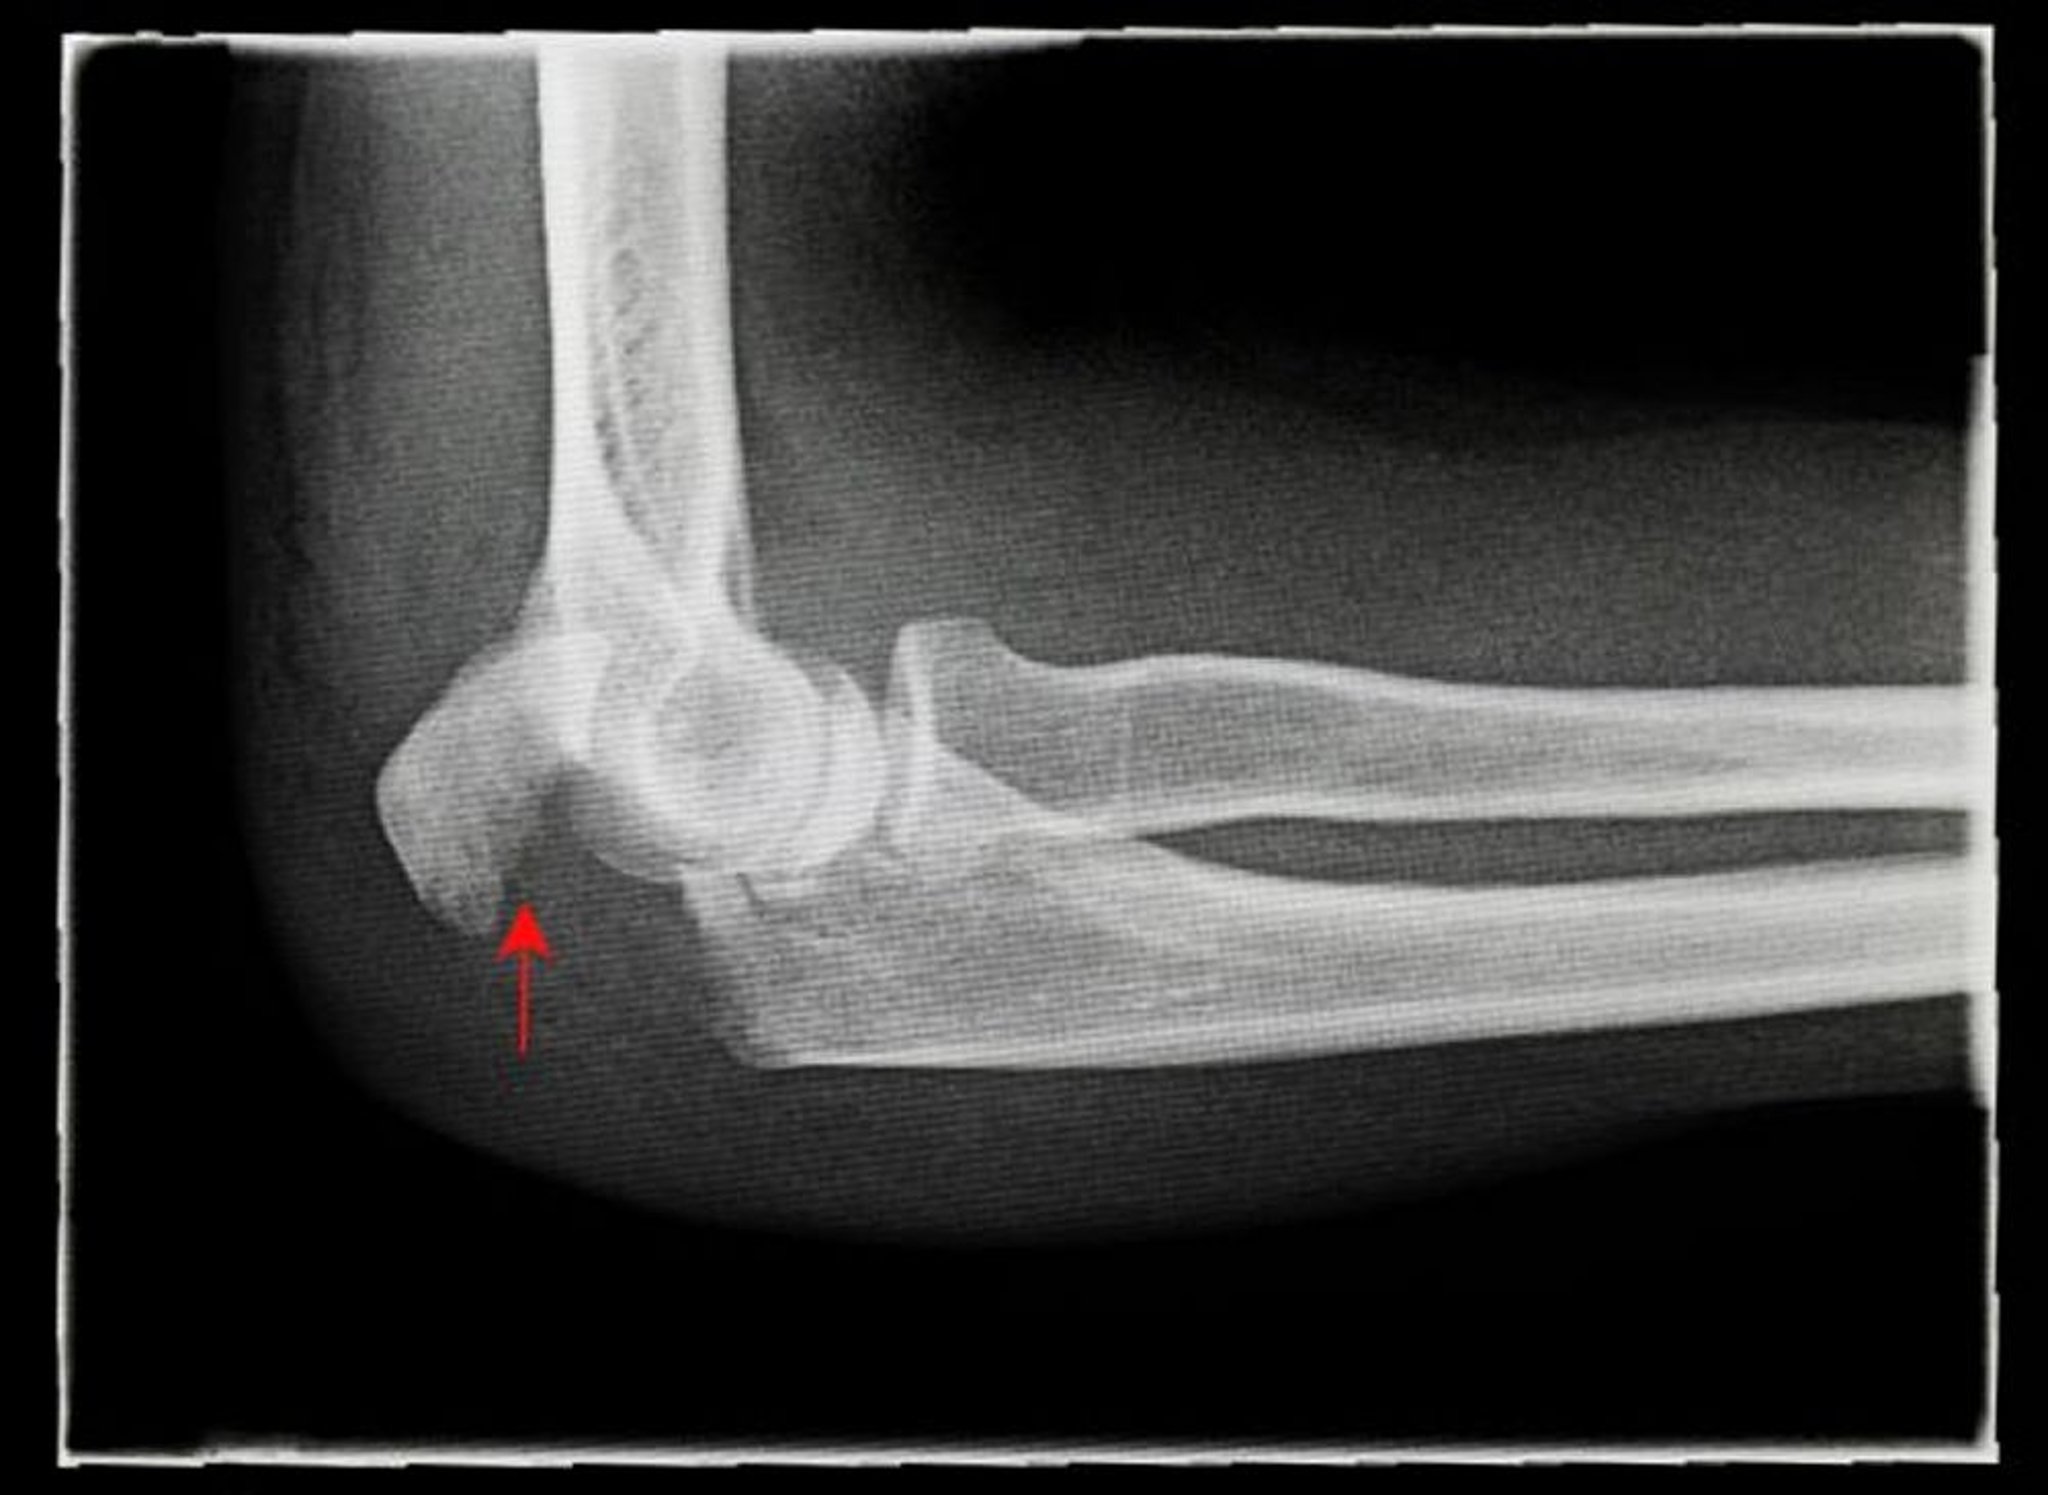

Esta radiografía muestra una vista lateral de una fractura desplazada del olécranon (flecha).

ANTONIA REEVE/SCIENCE PHOTO LIBRARY